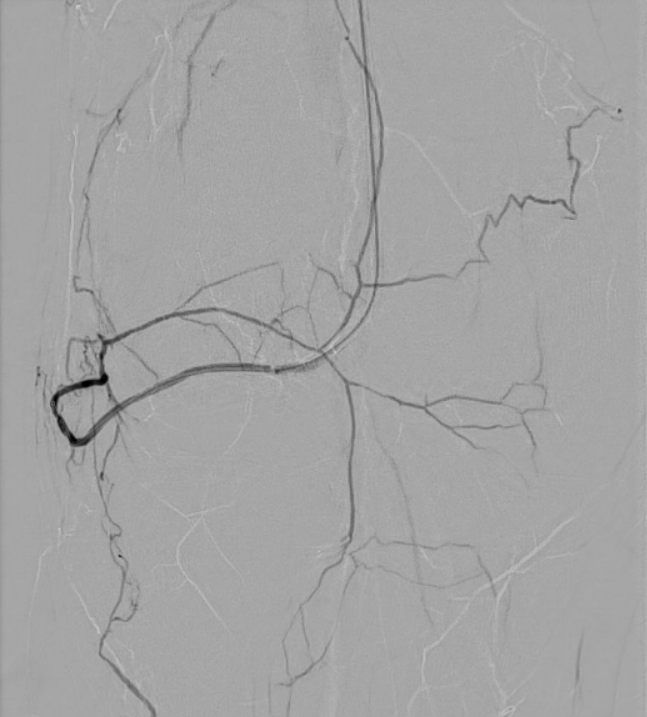

Das Verfahren beginnt mit einer kathetergestützten Zugangstechnik, bei der ein kleiner Katheter über eine Arterie eingeführt wird. Diese Katheter haben einen Durchmesser zwischen 1,5 und 2,5 mm und sind deshalb besonders gewebeschonend. Der Zugang der Behandlung erfolgt meist über die Leistenarterie oder einer Arterie am Arm (je nach dem Ziel der Behandlung). Die Katheter werden dann röntgengestützt bis zur behandlungsbedürftigen Region vorgeschoben. Dieses Verfahren ähnelt dem eines Herzkatheters. Nach Lokalisierung des Zielortes werden superselektiv die kleinsten Gefäße, welche für die Schmerzauslösung verantwortlich sind, mit einem Mikrokatheter (0,5 mm) sondiert. Es erfolgt dann Freisetzung der Mikroemboli, um die Blutzufuhr zu diesen spezifischen Bereichen zu blockieren. Diese Prozedur dauert zwischen 10-30 Minuten (je nach Erfahrung des Arztes und der Komplexität der Anatomie).

Nach Zurückziehen der Katheter wird die Zugangsstelle entweder mit einem Verschlusssystem verschlossen oder händisch komprimiert, um eine Blutstillung zu erreichen. Ein Druckverband wird angelegt, welcher in der Regel für 4-6 Stunden belassen wird. Bei einem Zugang über die Leistenarterie sollte zunächst Bettruhe eingehalten werden. Wenn über eine Armarterie punktiert wird, kann man nach der Behandlung problemlos aufstehen (unter Schonung des Armes).